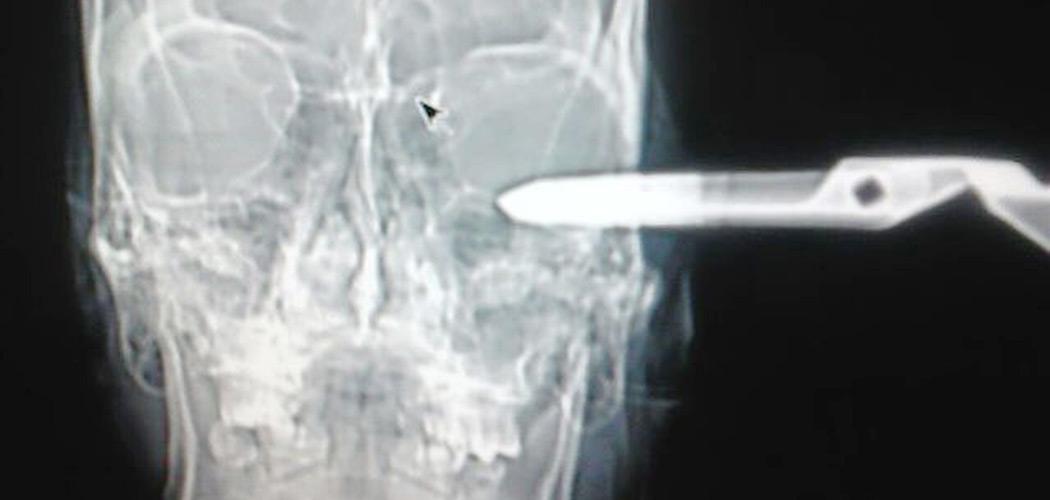

Voici des radiographies impressionnantes de la tête de M. Monroy :

Curieux ! Les deux radios montrent les ciseaux dans la même position alors que les clichés sont, un de face et l'autre de profil ????????

Ils sont peut être plantés de biais les ciseaux, ce qui expliquerait les radios.

CHIHUAHUA – Le gérant d’un bar au Mexique s’étant fait planter une paire de ciseaux dans la tête, s’est rendu aux urgences d’un hôpital et a expliqué très sereinement et poliment avoir un léger problème, avant d’être pris en charge par les médecins…

En effet, M. Armendariz a commencé à hausser le ton pour une raison inconnue et a sorti une paire de ciseaux de sa poche. M. Monroy lui a alors proposé un verre gratuit pour qu’il se calme, mais rien n’y a fait… M. Armendariz lui a planté les ciseaux en pleine tête et a pris la fuite.

Son ami présent aux moments des faits l’a alors conduit à l’hôpital le plus proche, où une fois sur place le gérant du bar s’est présenté à l’accueil en expliquant « avoir un petit problème et savoir si la réceptionniste pouvait l’aider ». Il a ensuite été pris en charge par les médecins qui ont heureusement pu le guérir, précise l’information parue sur le site du NY Post.

Son surprenant sang-froid et sa politesse compte tenu des circonstances lui ont valu d’être surnommé « El caballero » (« le chevalier » en français) par l’équipe médicale de l’hôpital, qui a expliqué que l’homme avait été très chanceux !